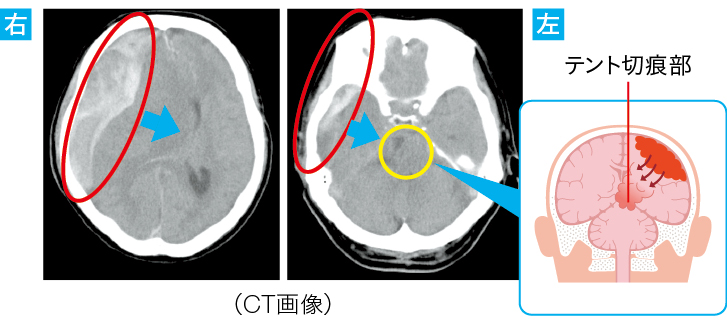

■「外傷性硬膜下血腫」を原因とした“テント切痕ヘルニア

●CT画像により、血腫により脳組織が圧迫され、増大に伴い、圧迫を受けた組織が押し出され、脳ヘルニアに移行(テント切痕ヘルニア)したことが確認された

●転倒時の頭部打撲により頭蓋内で出血(硬膜下血腫)が起こったことが推察された

●脳ヘルニアを疑って画像を見るポイント

midline shiftがないかを画像で見る際のポイントを紹介しています。